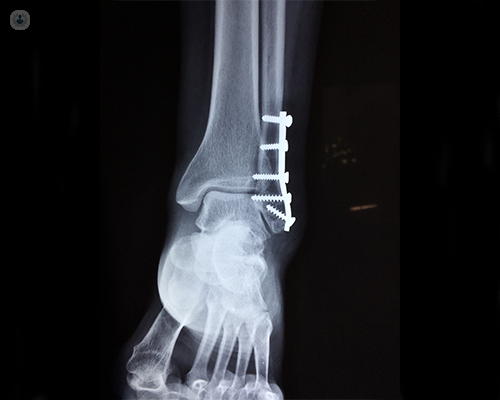

May surgery be required to heal these complex injuries?

Orthopaedic injuries place the patient at risk for various complications, including fat embolism, pneumonia, deep vein thrombosis, and sepsis. Many studies have documented the benefits of early stabilization in reducing morbidity and mortality. Early definitive long bone fixation and external fixation methods have evolved and are considered an integral part of the initial care.

Innovative techniques like computer-assisted surgery continues to develop as technology improves. Uses in trauma include navigation for percutaneous screw placement in trauma surgery and for replacement surgery for reconstruction of complex fractures.

The ultimate target is to enable patients to return to their pre-injury levels. Surgery might be the only option in many of the complex trauma presentations. All these patients should be managed in a collaborative manner. Better understanding and identification of these injuries enables us to optimise the outcomes.